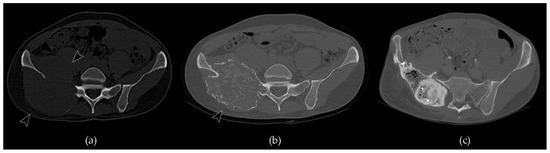

- Engellau, J.; Seeger, L.; Grimer, R.; Henshaw, R.; Gelderblom, H.; Choy, E.; Chawla, S.; Reichardt, P.; O’Neal, M.; Feng, A.; et al. Assessment of denosumab treatment effects and imaging response in patients with giant cell tumor of bone 11 Medical and Health Sciences 1103 Clinical Sciences. World J. Surg. Oncol. 2018, 16, 191. [Google Scholar] [CrossRef] [PubMed]

- van Langevelde, K.; van Vucht, N.; Tsukamoto, S.; Mavrogenis, A.F.; Errani, C. Radiological Assessment of Giant Cell Tumour of Bone in the Sacrum: From Diagnosis to Treatment Response Evaluation. Curr. Med. Imaging Former. Curr. Med. Imaging Rev. 2021, 17. [Google Scholar] [CrossRef] [PubMed]

- Oguro, S.; Okuda, S.; Sugiura, H.; Matsumoto, S.; Sasaki, A.; Susa, M.; Morioka, H.; Jinzaki, M. Giant cell tumors of the bone: Changes in image features after denosumab administration. Magn. Reson. Med. Sci. 2018, 17, 325–330. [Google Scholar] [CrossRef]

- Yonezawa, N.; Murakami, H.; Demura, S.; Kato, S.; Yoshioka, K.; Takeuchi, A.; Shinmura, K.; Yokogawa, N.; Shimizu, T.; Oku, N.; et al. Morphologic Changes after Denosumab Therapy in Patients with Giant Cell Tumor of the Spine: Report of Four Cases and a Review of the Literature. World Neurosurg. 2019, 127, 38–46. [Google Scholar] [CrossRef]

- Alothman, M.; Althobaity, W.; Asiri, Y.; Alreshoodi, S.; Alismail, K.; Alshaalan, M. Giant cell tumor of bone following denosumab treatment: Assessment of tumor response using various imaging modalities. Insights Imaging 2020, 11, 41. [Google Scholar] [CrossRef] [PubMed]

- van Langevelde, K.; McCarthy, C.L. Radiological findings of denosumab treatment for giant cell tumours of bone. Skelet. Radiol. 2020, 49, 1345–1358. [Google Scholar] [CrossRef]

- Campanacci, L.; Sambri, A.; Medellin, M.R.; Cimatti, P.; Errani, C.; Donati, D.M. A new computerized tomography classification to evaluate response to Denosumab in giant cell tumors in the extremities. Acta Orthop. Traumatol. Turc. 2019, 53, 376–380. [Google Scholar] [CrossRef] [PubMed]